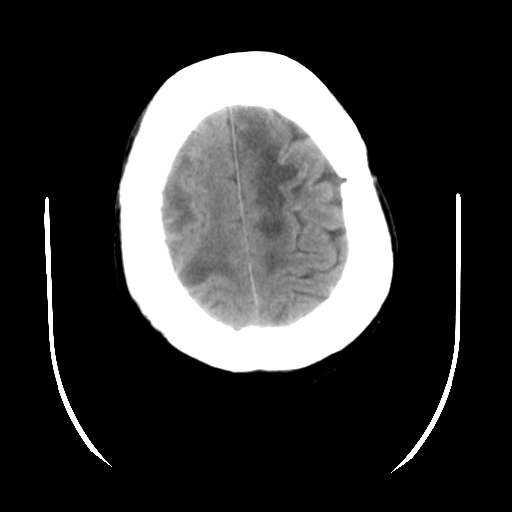

以下是引用随光逐影在2009-4-11 0:07:00的发言:[br]12天前ct检查:1)蛛网膜下腔出血。2)脑室系统少量积血。3)脑积水。[br]今日ct检查:1)多发性脑梗塞,伴部分梗塞区脑皮质渗血。2)脑积水。[br]